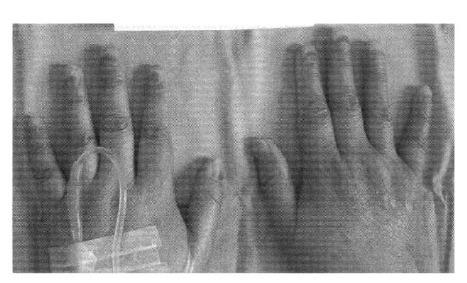

Nail toxicity following systemic chemotherapy is common. Onychopathy during the period of neutropenia following chemotherapy may cause subungual abscesses and serious infection. Despite taxoid-related toxicity being increasingly reported since 2000, there are still phase II systemic chemotherapy studies using taxoid that have never mentioned nail changes. Recently, new criteria for the evaluation of nail toxicity have been suggested. The present report is the first of its kind, in Korea, to describe a case of docetaxel-associated onychopathy, which improved following a reduction in the docetaxel dose.

全身化疗后出现指甲毒性很常见。化疗后中性粒细胞减少期间的指甲病变可能导致甲沟炎和严重感染。尽管自2000年以来越来越多地报道了紫杉类药物相关的毒性,但仍有一些使用紫杉类药物的II期全身化疗研究从未提及指甲变化。最近,有人提出了评估指甲毒性的新标准。本报告是韩国首例描述多西他赛相关性指甲病变的病例,该病例在多西他赛剂量减少后有所改善。